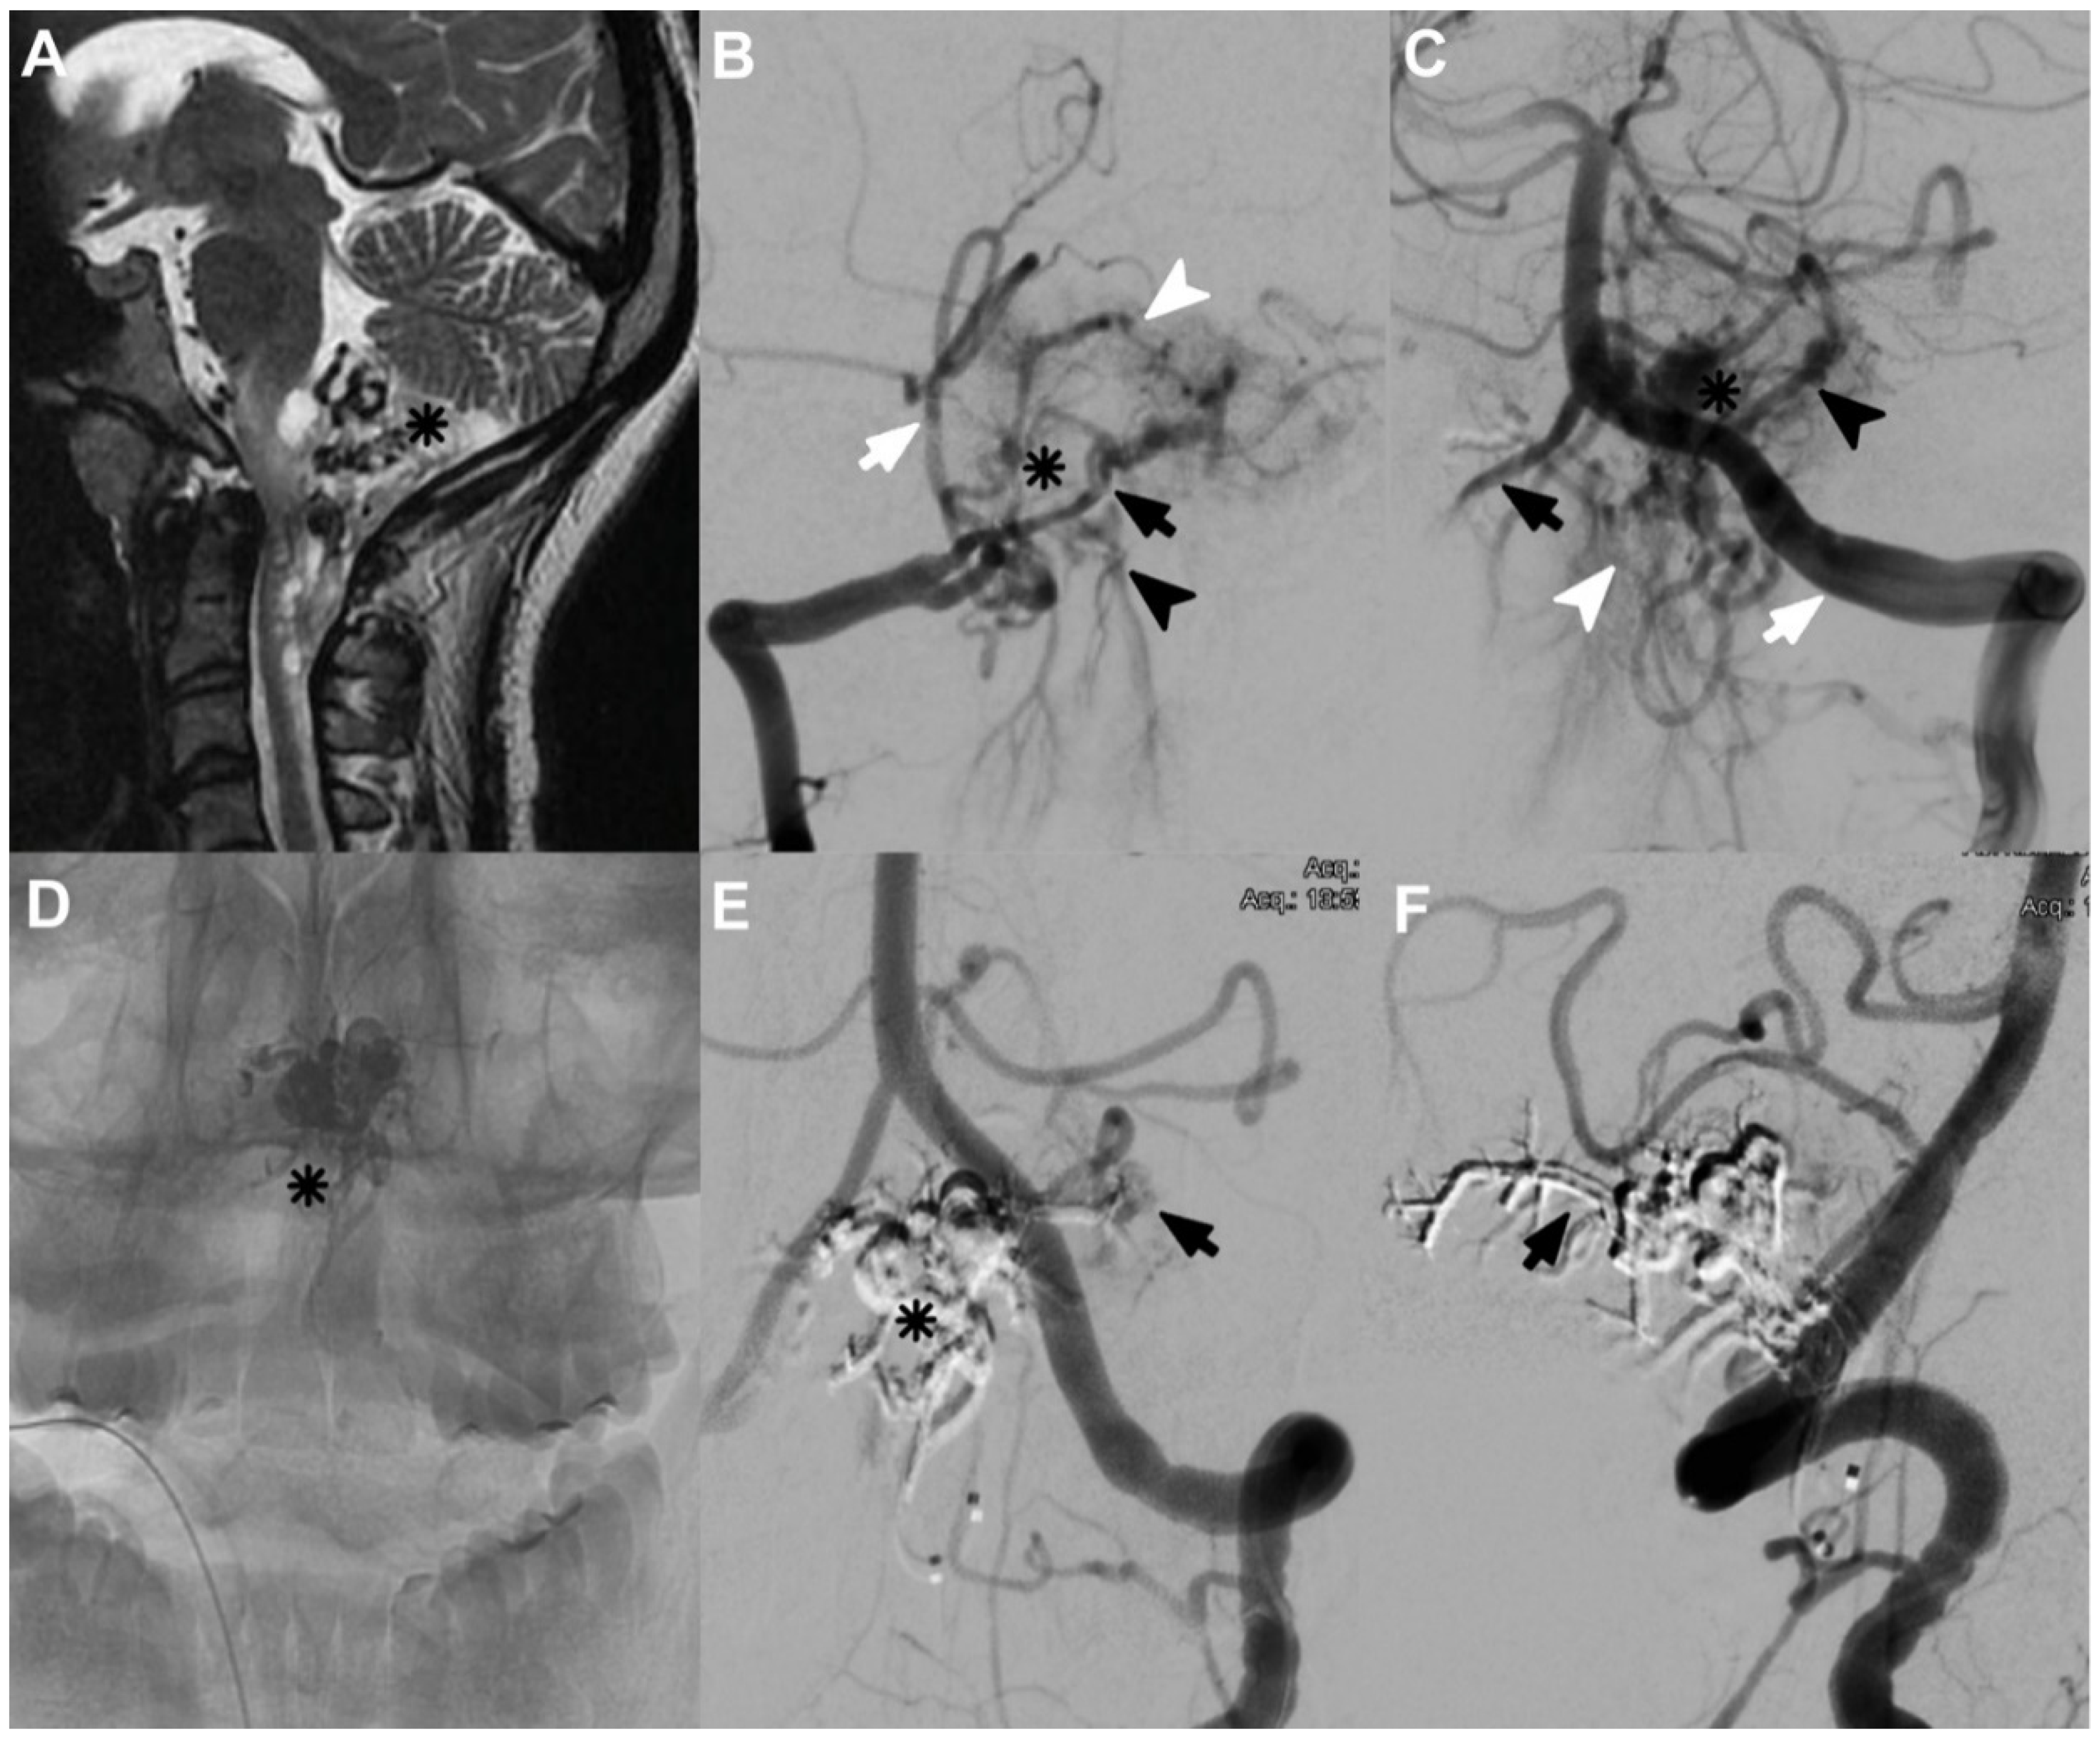

Case 8 was a 26-year-old female with a history of two syncopal episodes. The MRI showed void signals at the CCJ. Angiography resulted in CCJ AVF (Figure 3A), with feeders from PSA, which arose from extracranial PICA on the right side and RMA with posterior meningeal branches from V3 on the left side. We identified two arterial aneurysms, and the drainage was toward marginal sinus and subdural veins (Figure 3B,C). In the first session, we embolized with Histoacryl through the right PSA (Figure 3D). The second session was through a left RMA. Angiographic control one year later showed a very small remnant of CCJ AVF (Figure 3E,F), but the patient did not develop any neurological deficit.

Figure 3.

(A) The T2 MRI of a complex AVF of the CCJ (asterisk). (B) The AP DSA of the right vertebral artery (VA); an extracranial PICA is noted (white arrow), as is a small arterial aneurysm (asterisk). Hypoplasia of the V4 segment (black arrow) and an arterial shunt (white arrowhead) are also evident. Venous drainage towards the marginal sinus and the extradural venous plexus (black arrowhead) can also be observed. (C) The AP left VA (white arrow); the hypoplastic right VA is noted (black arrow). Furthermore, the intradural PICA (black arrowhead), the dysplastic aneurysm (asterisk), and the extradural venous drainage (white arrowhead) can be observed. (D) Histoacryl on fluoroscopy. (E) The obstructed CCJ AVF, including the aneurysm (asterisk), is shown, but a small residual component can be noted (black arrow). (F) The left VA, showing the patency of the PICA, but a complete occlusion of the posterior meningeal artery (black arrow).